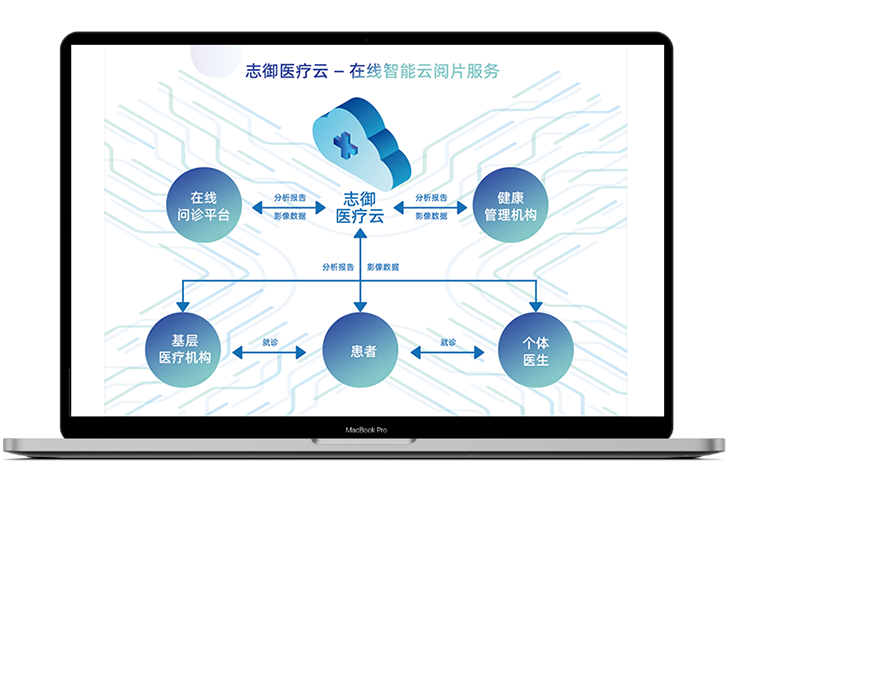

志御科技致力于成為全球肝

腦醫療AI領域的創新引領者

上海志御軟件信息有限公司(簡稱:志御科技)是中國領先的高科技醫療AI創新企業,創始團隊由知名醫學影像科學家隊伍及世界500強企業資深管理和營銷精英組成。公司致力于成為全球肝、腦醫學影像AI分析、AI輔助診斷以及AI遠程醫療的創新引領者,打造肝、腦醫療AI第一品牌。

閱讀更多